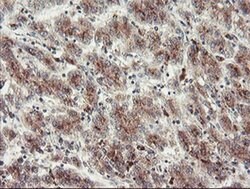

ACBD3 Monoclonal Antibody for Western Blot, IHC (P), Flow

| Flow Cytometry, Immunohistochemistry (Paraffin), Western Blot | |